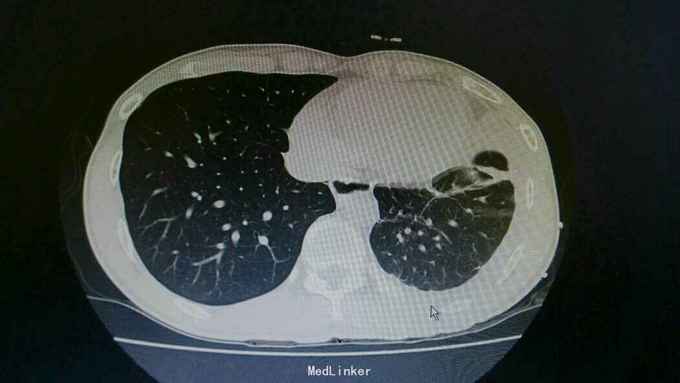

诊断:结核性胸膜炎 治疗:入院予以左侧胸水引流,T-SPORT A68,B24。予以四联抗结核治疗。辅查胸部CT患者左侧胸水减少,病情好转。